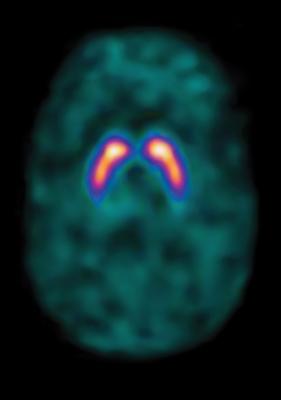

Pin On Brain